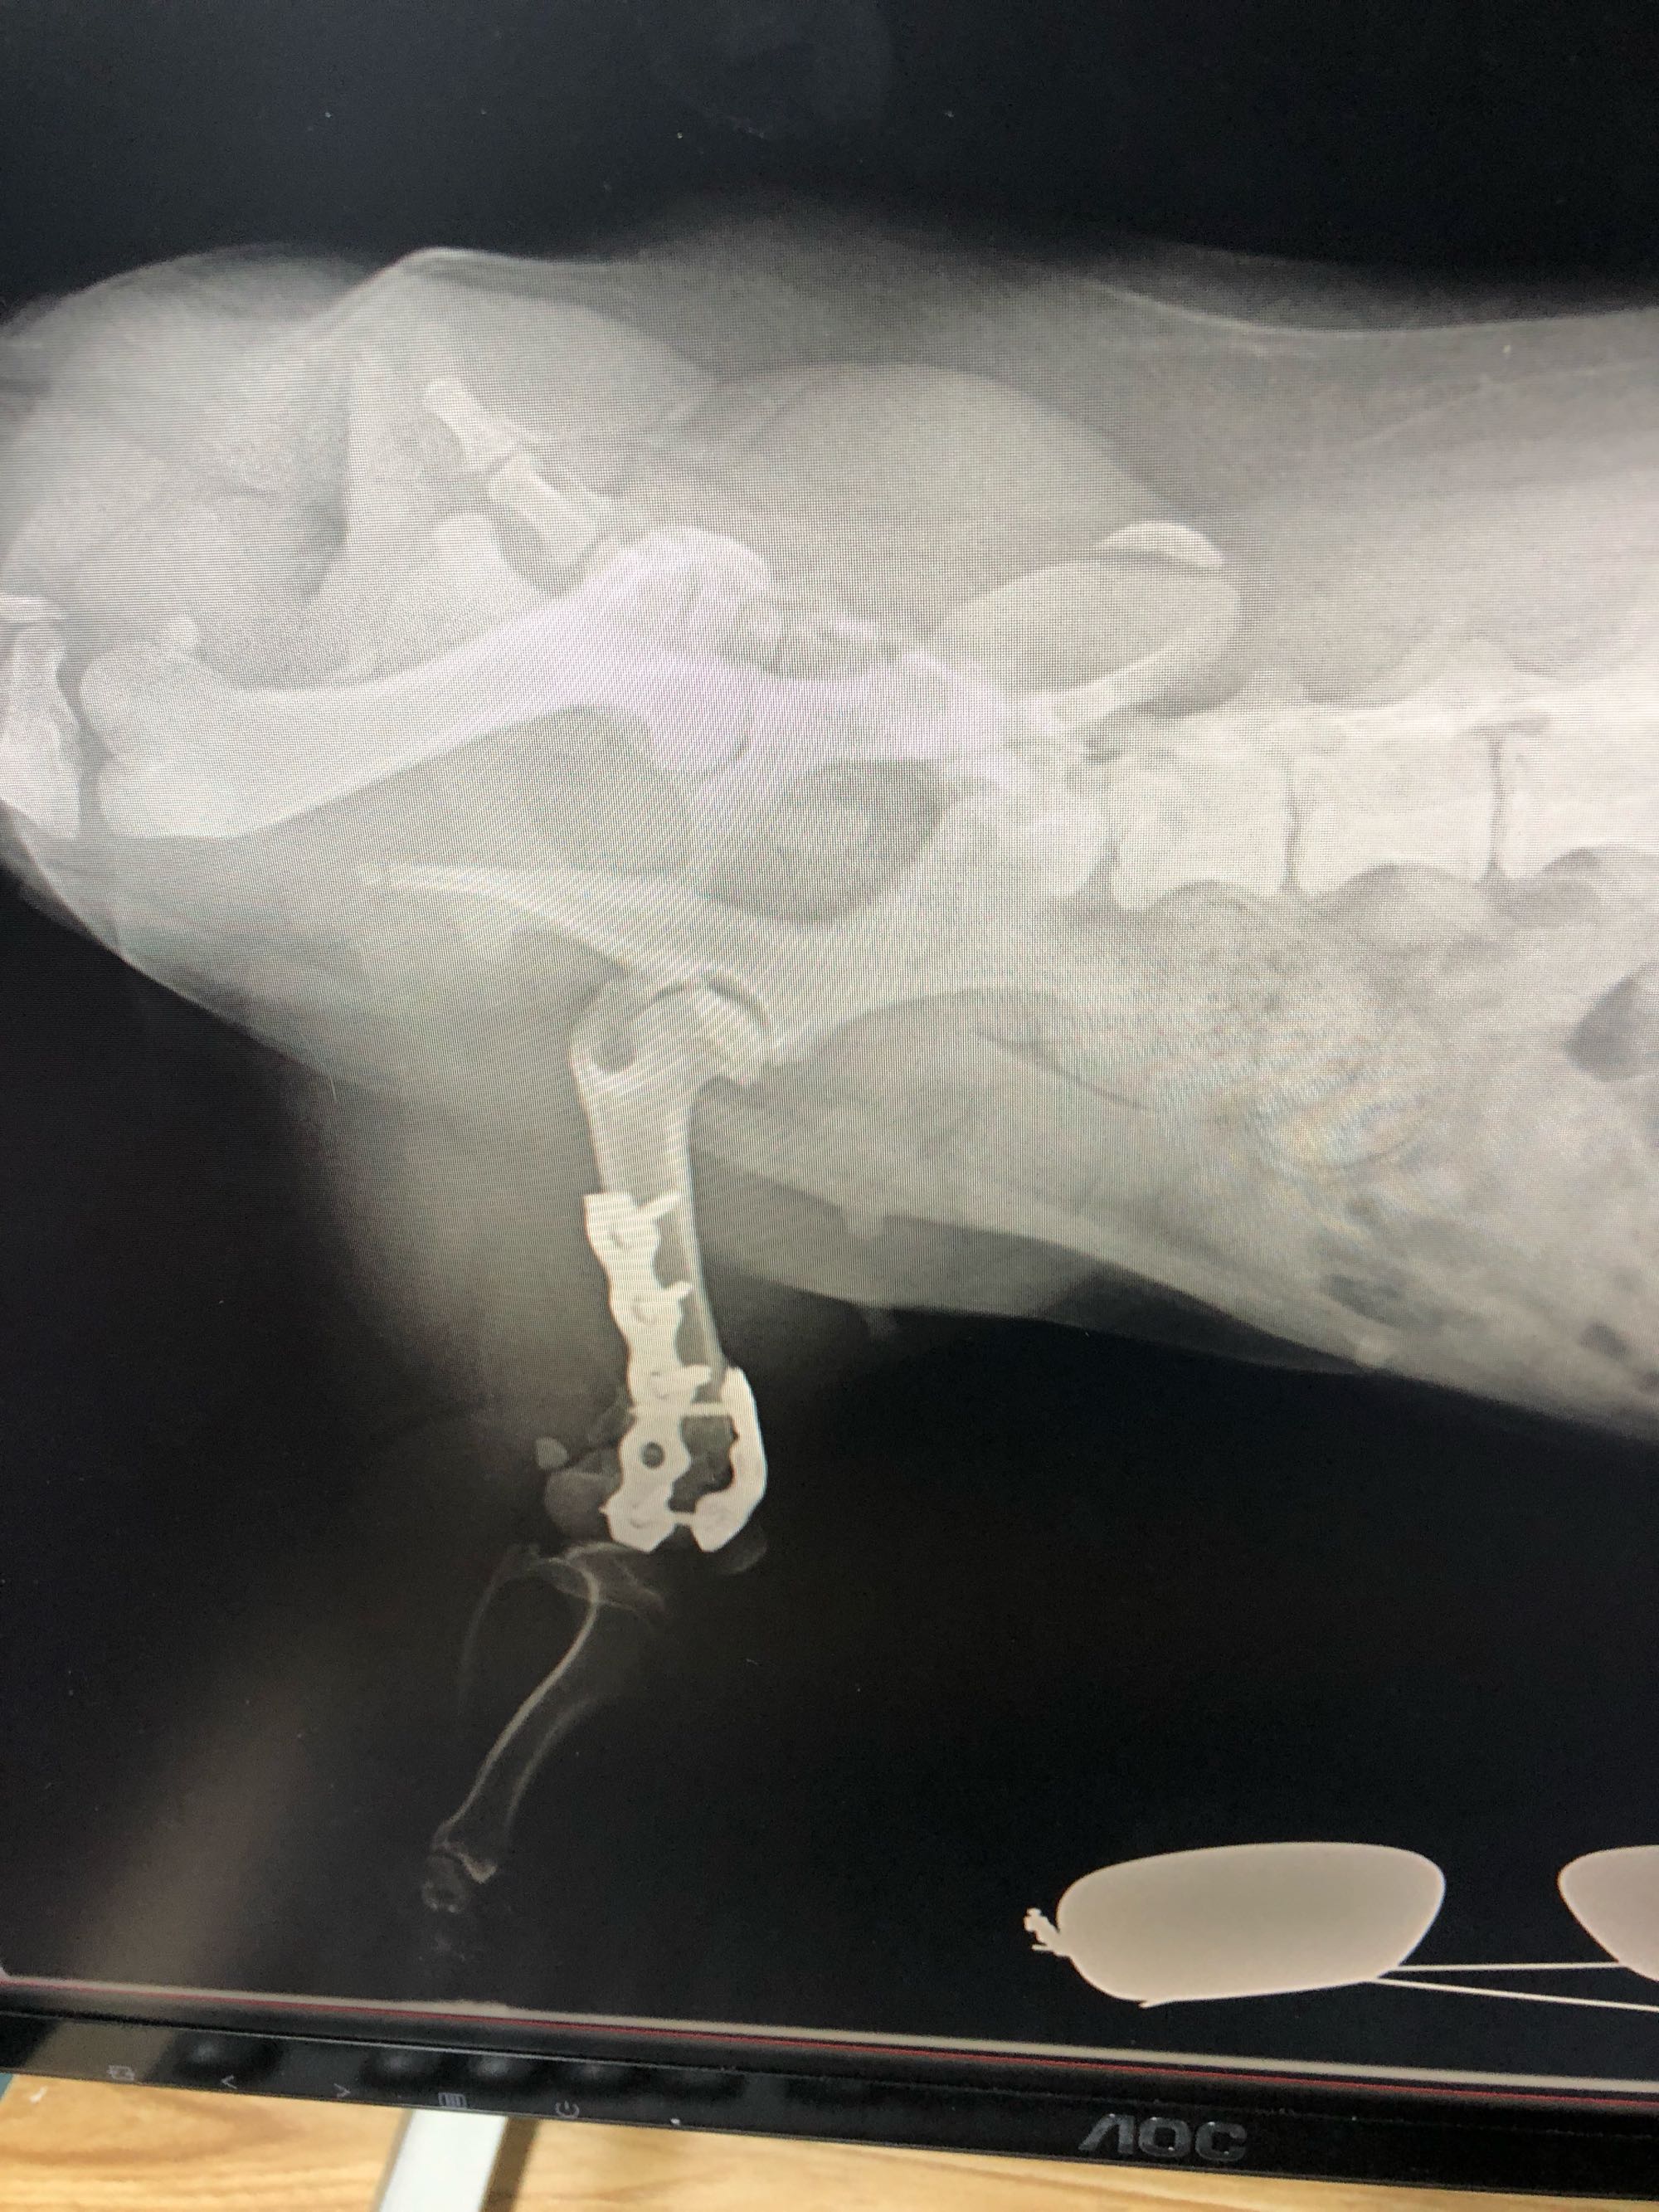

骨折完美复位的小柯基,医生们技术真到位

你好,是做手术复位?还是??